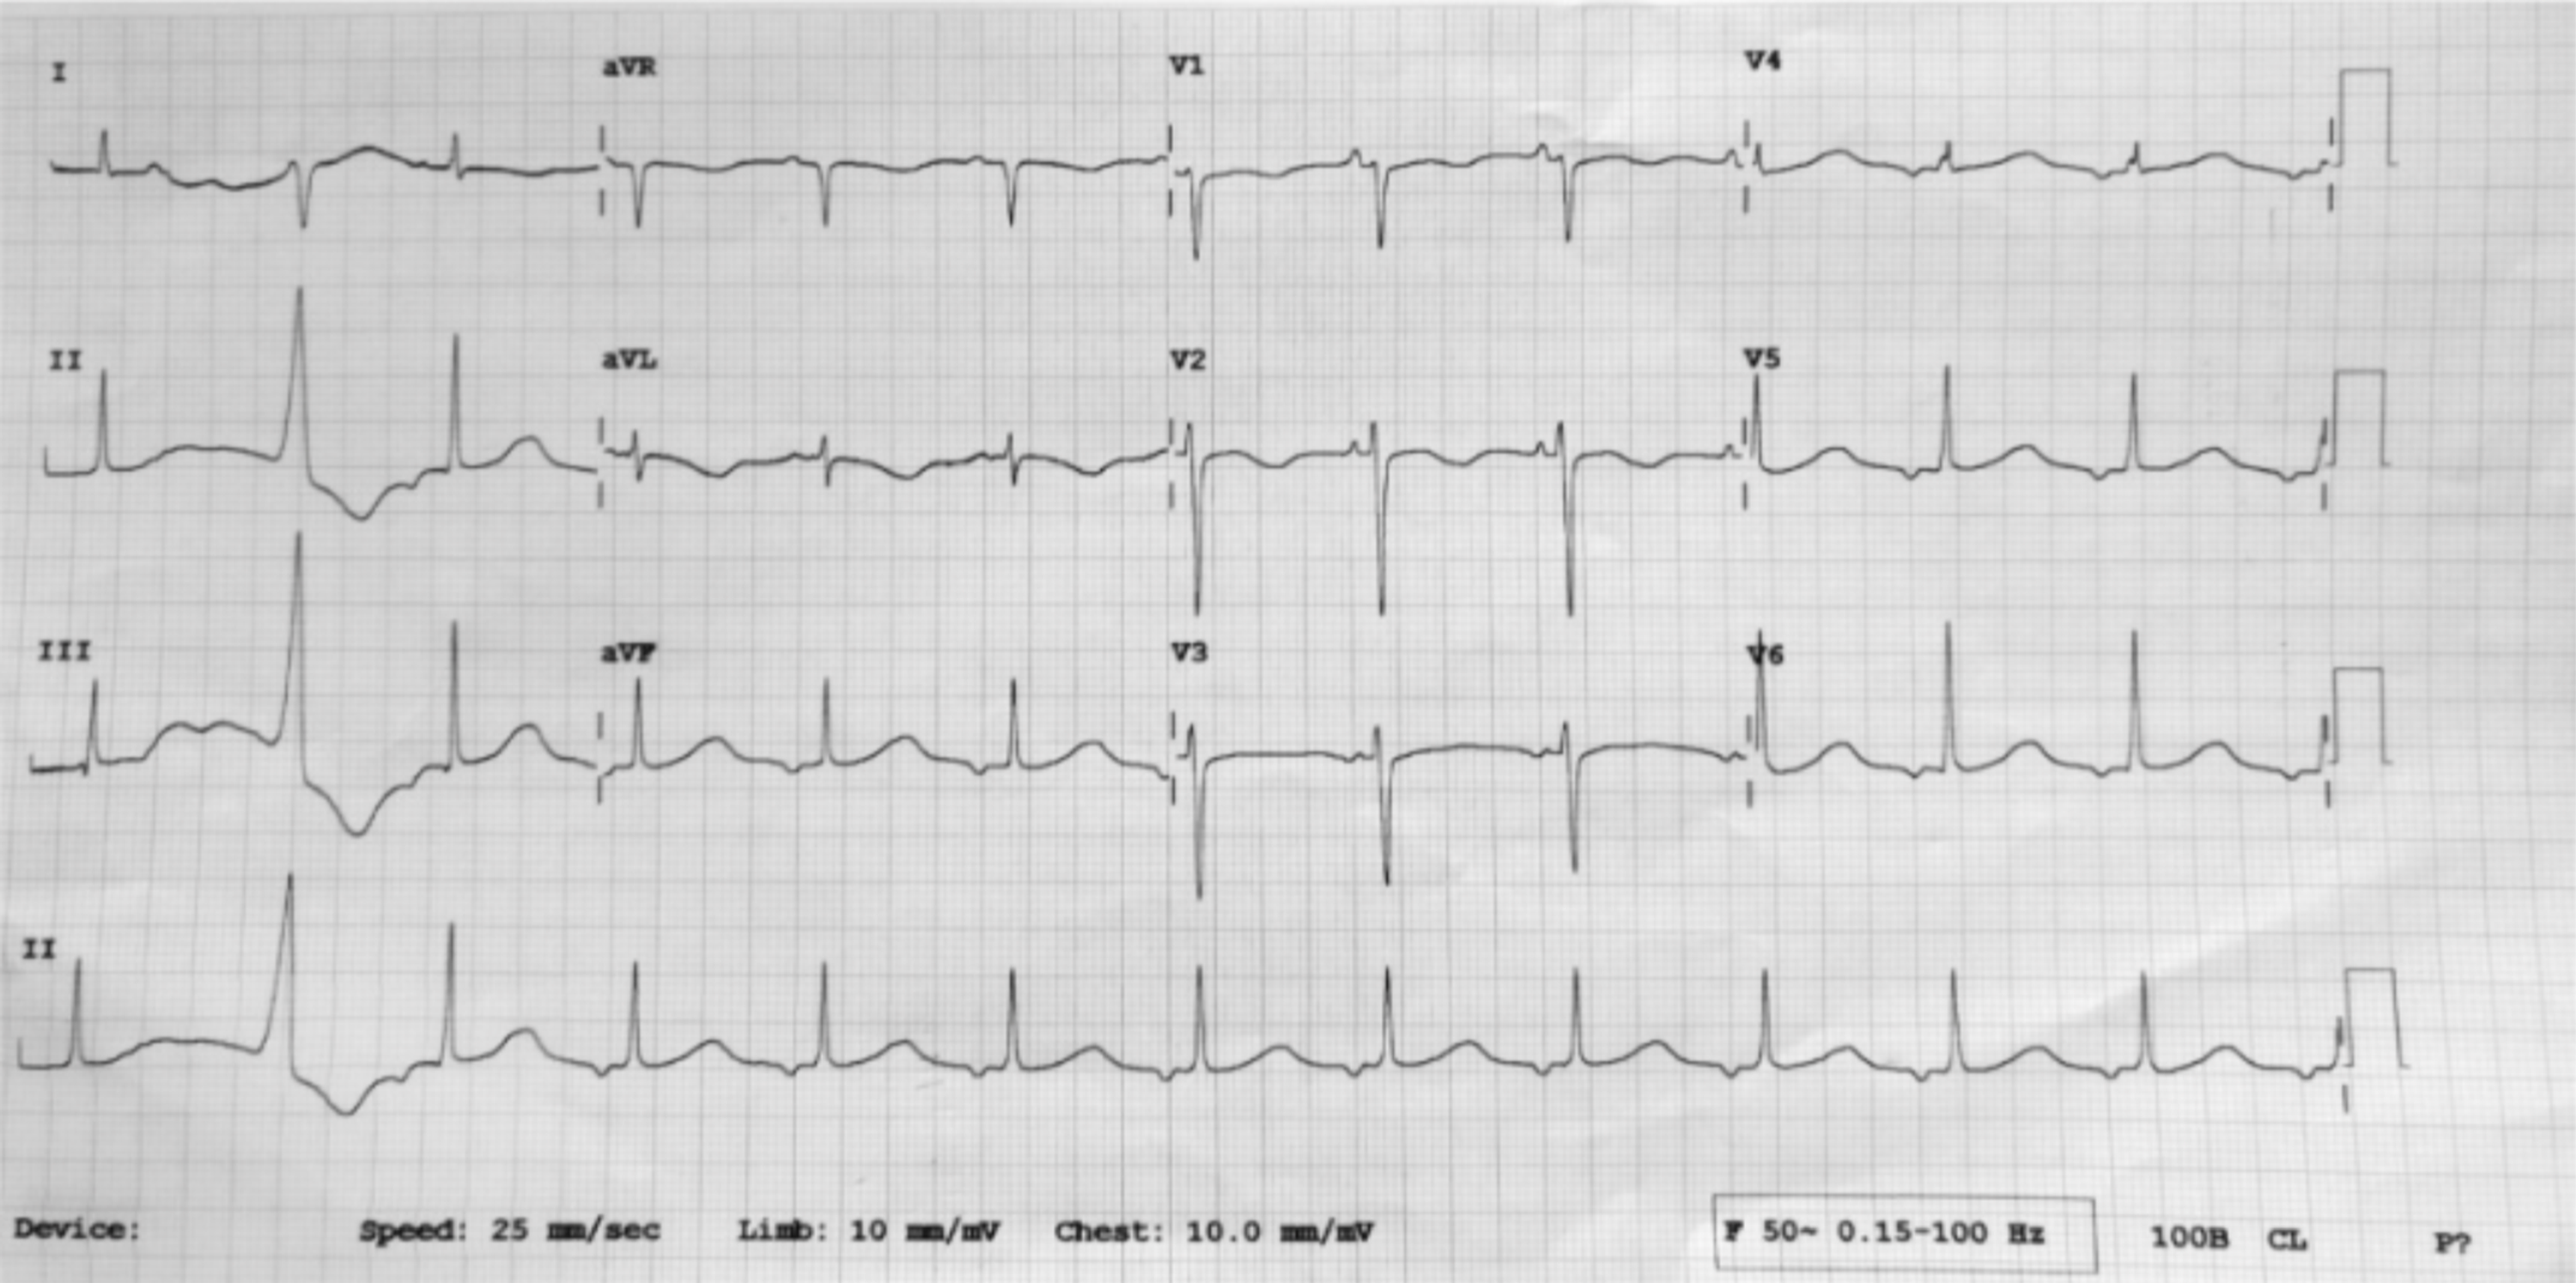

Elettrocardiogram. Prolonged QT interval. Download Scientific Diagram Low Magnesium Prolonged Qt Hypomagnesemia is defined as a serum magnesium concentration that is below the normal range (eg, less than 1.7 mg/dl in. A comprehensive list of conditions and drugs that may prolong the qt interval, cause torsade de pointes (tdp) and long qt syndrom. If a ventricular ectopic beat occurs during this repolarization period, torsades can be triggered. In the setting of. Low Magnesium Prolonged Qt.

ECG Rhythms Prolonged QTc due to hypocalcemia Low Magnesium Prolonged Qt Long qt syndrome (lqts) is a heart rhythm disorder that causes fast, chaotic heartbeats. Serum potassium, calcium, and magnesium levels should be checked, as low. Hypomagnesemia is defined as a serum magnesium concentration that is below the normal range (eg, less than 1.7 mg/dl in. A comprehensive list of conditions and drugs that may prolong the qt interval, cause torsade. Low Magnesium Prolonged Qt.

Hypomagnesaemia ECG changes • LITFL • ECG Library Low Magnesium Prolonged Qt Serum potassium, calcium, and magnesium levels should be checked, as low. Hypomagnesemia is defined as a serum magnesium concentration that is below the normal range (eg, less than 1.7 mg/dl in. In the setting of a prolonged qt interval this repolarization process takes longer. If a ventricular ectopic beat occurs during this repolarization period, torsades can be triggered. A comprehensive. Low Magnesium Prolonged Qt.

Dr. Smith's ECG Blog Potassium and Magnesium how low is too low? Low Magnesium Prolonged Qt Long qt syndrome (lqts) is a heart rhythm disorder that causes fast, chaotic heartbeats. Hypomagnesemia is defined as a serum magnesium concentration that is below the normal range (eg, less than 1.7 mg/dl in. In the setting of a prolonged qt interval this repolarization process takes longer. If a ventricular ectopic beat occurs during this repolarization period, torsades can be. Low Magnesium Prolonged Qt.